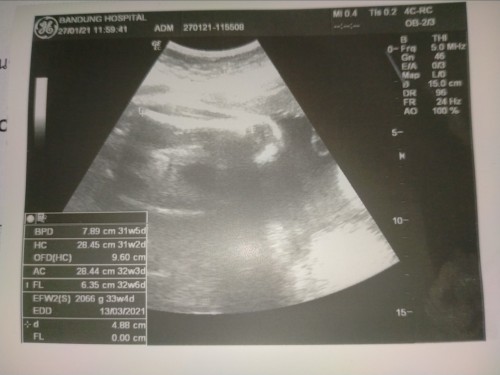

ขอสอบถามแม่ๆทุกท่านหน่อยจ้า เราสับสนกับการนับอายุครรภ์ของพยาบาลกับหมอที่ไม่ตรงกันมากเลย คือเราไปฝากครรภ์ครั้งแรกวันที่ 21 กันยายน63 หมอใหญ่ อัลตราซาวด์ให้ ได้ 10วีคกับอีก2วัน ซึ่งถ้าถึงวันที่30ตุลาคือวันนี้ เราจะต้องได้16วีคกว่าแล้ว แล้ววันนี้หมอนัด วันที่30ตุลาคม2563 พยาบาลที่ซักประวัติ ดันบอกได้แค่14วีค กับอีก5วัน อ่าวสับสนละทีนี้ ทั้งที่เราจำรอบเดือนขาดได้โครตแม่น และคิดว่านับได้ตรงกับหมอ #ขอคำแนะนำหน่อยค่ะ #ขอบคุณล่วงหน้านะคะ คือถ้าเราคิดเองแม่ๆว่าวันนี้30ตุลาคม จะได้14วีคกับอีก5วันจริงหรอ ???????